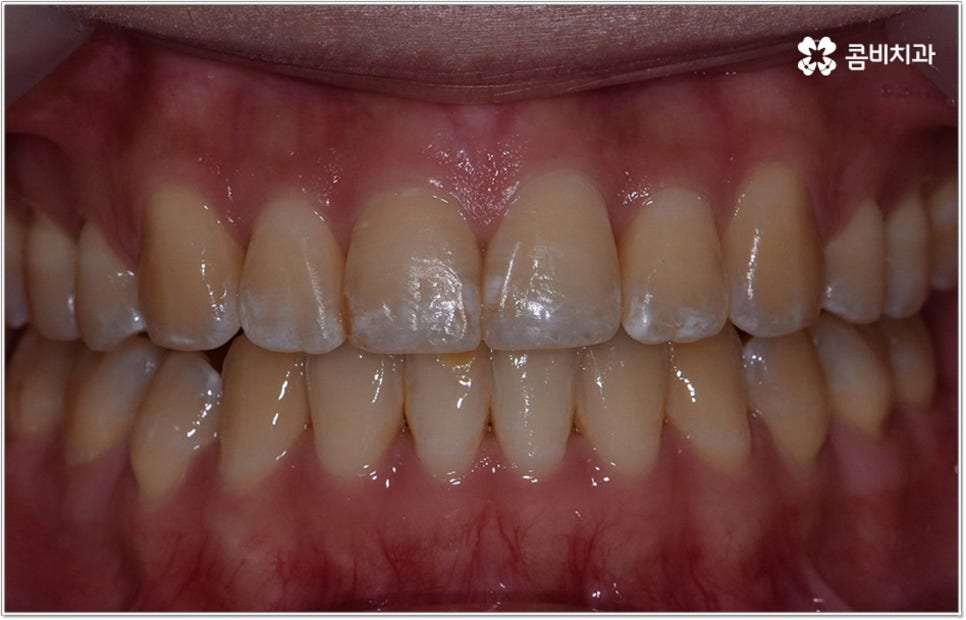

잘 아시다시피 교정이란 치아에 교정 장치 (브라켓) 를 부착하고 와이어에 교정력을 걸어 필요한 방향으로 치아를 이동시킴으로써 고른 치열과 올바른 교합을 가진 정상적인 구강 구조를 회복하는 치과 진료를 의미하는데요, 말씀드린 것처럼 부정교합에는 다양한 형태가 있고 또한 환자분들마다 심각한 정도가 모두 다르기 때문에 현 상태를 면밀하게 체크하고 맞춤 교정 치료 계획을 세우는 것이 무엇보다 중요하다고 할 수 있습니다. 즉 3D CT 와 같은 정밀 진단 장비를 갖추고 있는 치과에서 교정 관련 임상 경험이 풍부한 숙련된 의료진과 함께 치료를 진행하는 것이 필수적이라고 할 수 있어요. 전체 방향 및 세부 플랜을 세울 때 각 환자에 맞게 치아의 이동 속도에 무리가 가지 않도록 하기 위해서 연령이나 발달 상황, 진행 상황을 면밀하게 살펴보는 것이 필요하며 또한 구강 내 공간 유무 및 부정교합 정도에 따라 발치 또는 비발치치아교정 여부를 결정하게 될 거예요.

만약 치아가 이동할 범위를 계산해 봤을 때 공간이 충분하다면 굳이 치아를 뽑지 않고 비발치치아교정 과정으로 치료할 수 있어요. 제일 뒤에 있는 어금니를 더 후방으로 이동시키거나 치간 삭제, 악궁확장장치 등으로 치아 사이를 벌려서 이동 공간을 확보할 수 있으면 비발치치아교정 이 가능한 거예요. 이 때 부정교합이 심각하거나 악골이 치아에 비해 많이 작은 경우, 구조적인 원인을 개선할 필요성이 있는 경우 등 발치 교정을 하는 것이 꼭 필요한 케이스라면 치아를 뽑아주어야 하며, 환자분들의 상황에 따라 다르지만 보통은 소구치를 발치하는 경우가 많이 있습니다.

대다수의 환자분들은 되도록 치아를 뽑지 않았으면 하고 바라시겠지만 발치교정이 꼭 필요한 케이스에서 비발치치아교정 을 고집하게 되면 치열을 원하는 정도까지 움직이기 어렵고 (예를 들어 만약 돌출입이라면 만족할 만한 수준까지 들어가지 않을 수도 있음) 결과적으로 상하 부정 교합 역시 제대로 개선되지 않을 수 있어요. 이 때 다양한 케이스를 다뤄보고 뛰어난 노하우를 가지고 있는 의료진과 충분히 상담을 해 보시고 또한 모르페우스를 이용하여 교정 치료를 받고 난 후의 미래 예상 모습을 살펴 보고 나면 발치 과정의 필요성에 대해 스스로 이해하는데 도움이 되실 거예요.